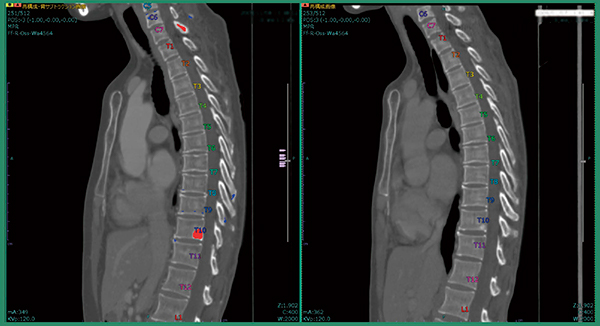

このソフトウエアでは,PACSから読み込んだCTの過去画像と今回画像の各椎骨を分離・同定し,非剛体位置合わせの上,差分を行う。その結果をカラー画像にして,今回画像に重ねて表示する。不透明度が上がった部分は寒色系,不透明度が下がった部分は暖色系で表現される。ある程度の大きさの骨転移病変ならば差分画像がなくても診断は容易だが,図1のような小さな病変(左横突起への骨転移)は,疼痛がない場合は経過観察で見逃してしまう可能性があり,ソフトウエアを用いた差分画像が役立つと言える。

図1 従来版ソフトウエアによる左横突起への骨転移候補の検出

症例1は,肺がん術後症例で肺の形が変形しており,撮影範囲も過去画像は胸部のみ,今回画像は胸腹部と大きく異なっていた。改良版ソフトウエアで差分を取ると,溶骨性の骨転移が青く表示され,椎骨が変形している様子もわかる(図2)。また,自動でラベリングされるため,椎骨番号の判断が容易となり,T4,T5であると判断できる(図3)。さらに,T1にも溶骨性の小さな骨転移があることが明瞭にわかる(図4)。

図3 症例1:椎骨番号の自動ラベリング